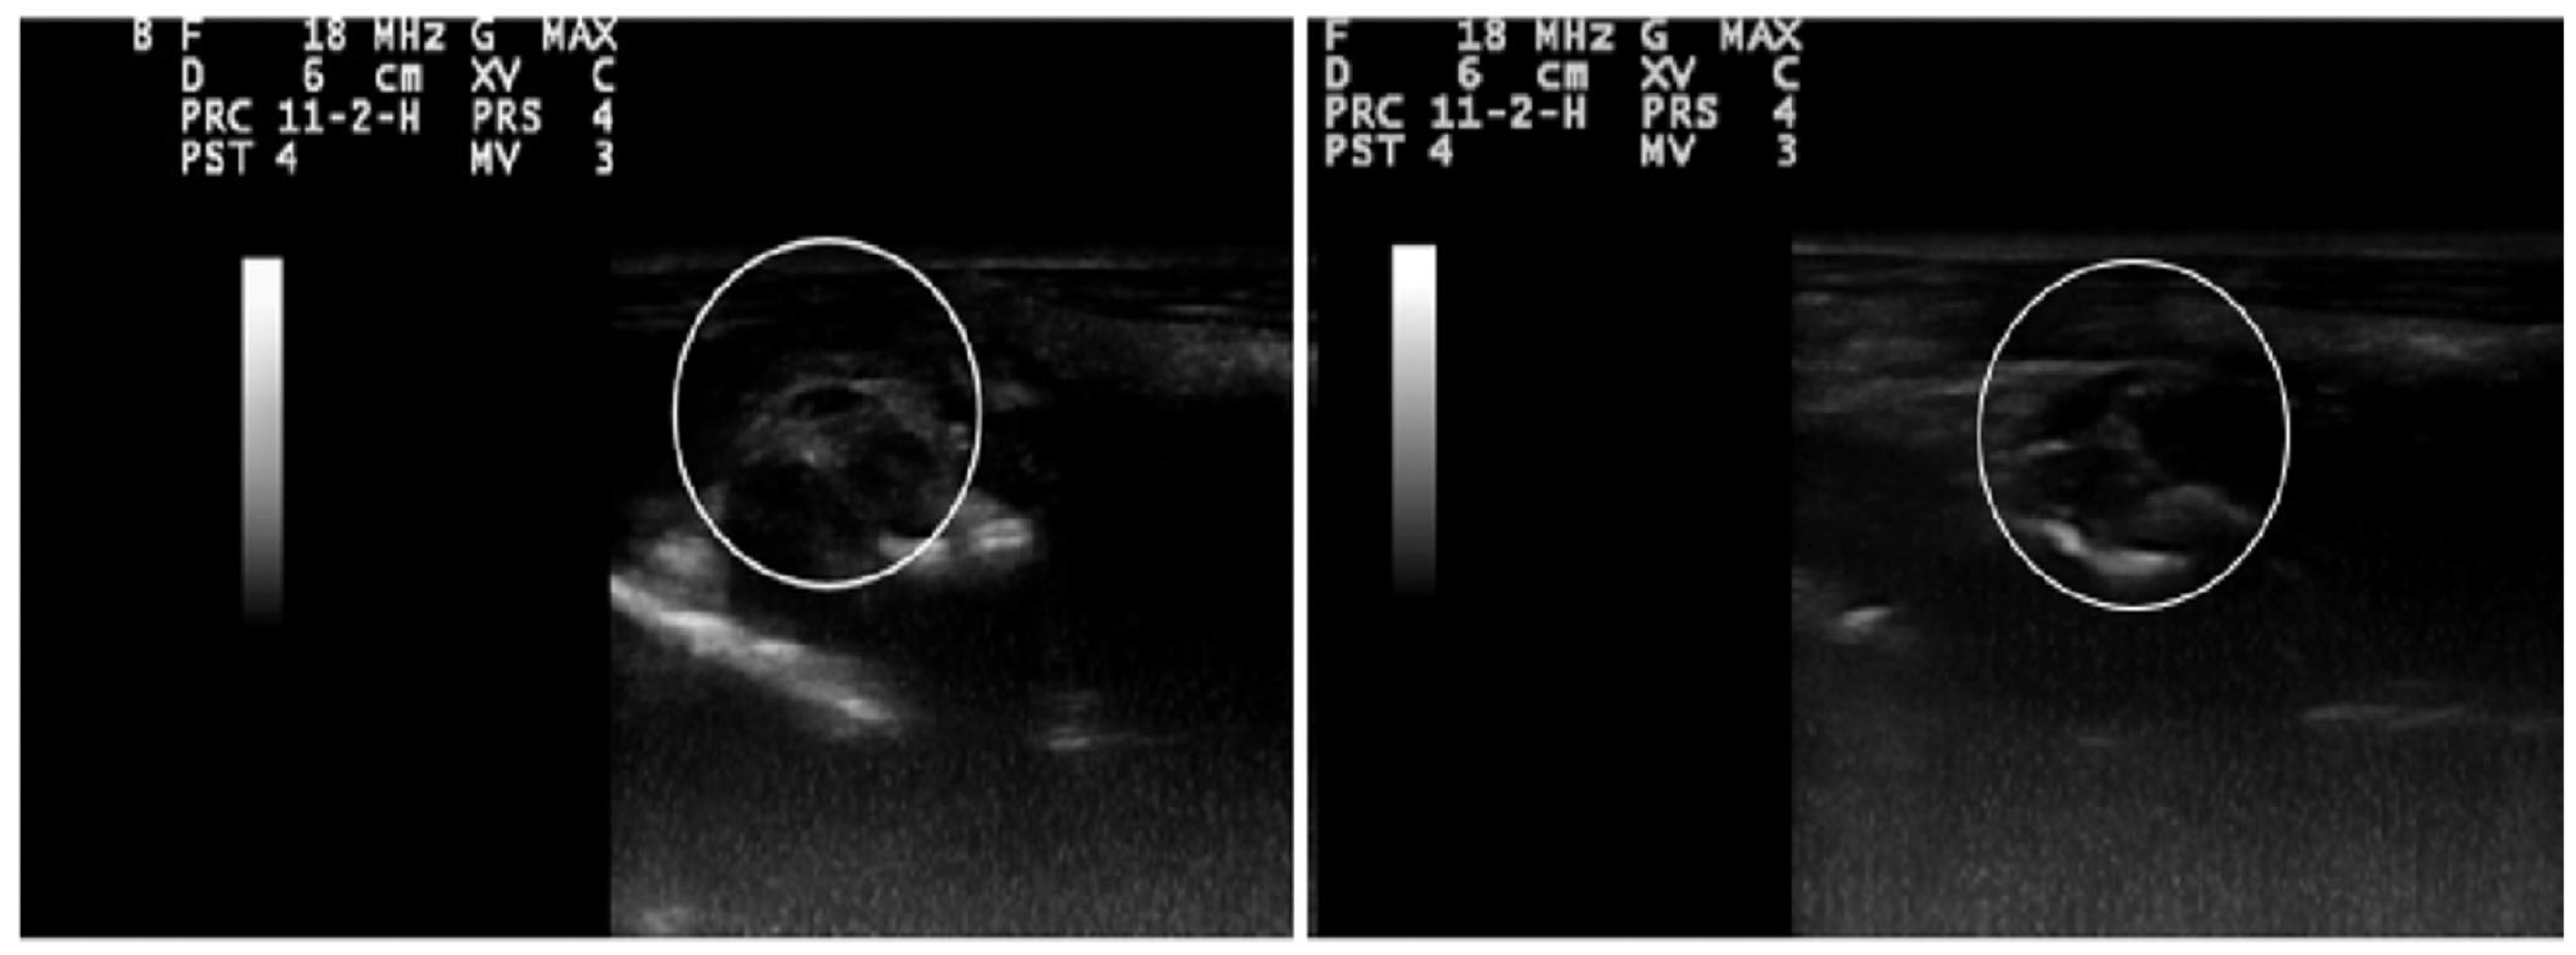

2.9. Ultrasonography Findings

4.9. Ultrasonographic Evaluation